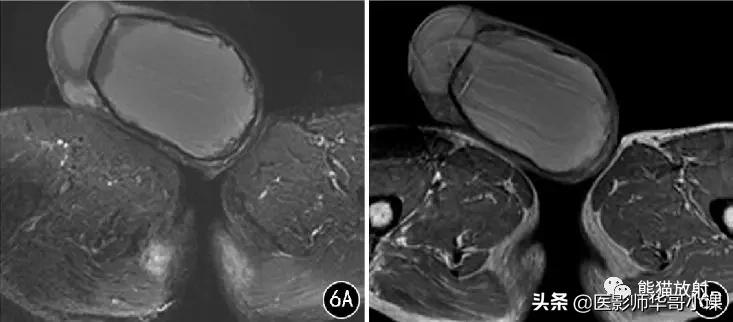

![[精品课件]畸胎瘤及精原细胞瘤(*丸睾**肿瘤及肿瘤样变CT及MR表现)](http://static.shicijianshang.com/origin/pgc-image/7ead4912973f479e87609a1aa5d86c9d.jpg)

图6 男,66岁, 左侧*丸睾**血肿 。左侧*丸睾**明显肿大,病灶呈T2WI 抑脂(A) 稍高信号,T1WI(B) 高信号,边缘见低信号包膜,包膜内壁多个壁结节突起。